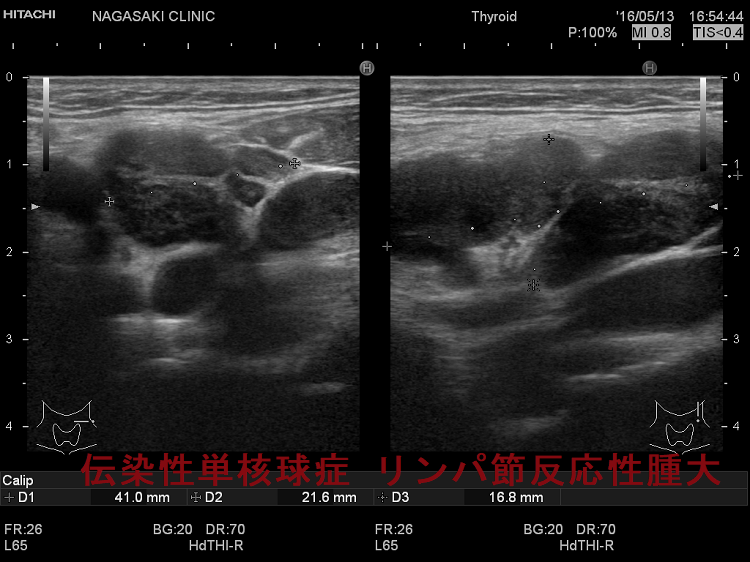

亜急性甲状腺炎と鑑別を要する伝染性単核球症。喉(のど)の痛みと首のリンパ節の腫れを甲状腺の病気と思って、長崎甲状腺クリニック(大阪)を受診される方がおられます。

- 痛みを伴う著明な後頸部リンパ節腫脹は1〜2週頃がピークで、耳下腺の下、外側頚部まで累々と広がり、全身のリンパ節も腫大します。

- 亜急性甲状腺炎と鑑別を要する伝染性単核球症を発症